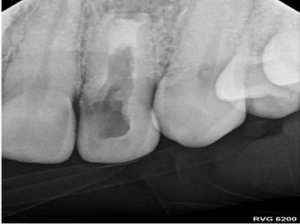

Our patient, a 57-year-old physician, came to us with a tooth that had likely experienced trauma when he was just seven or eight years old. Despite having undergone endodontic treatment in his youth, the tooth presented with some concerning issues:

- An apical lesion (an area of infection at the root tip)

- Immature root form

- Unusual placement of the previous treatment’s access filling